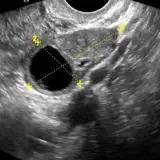

Over 2,100 interactive radiology cases, curated by radiologists for your level of training. Scroll, window, and view cases full screen โ€” just like on PACS. Click linked findings in each writeup to jump straight to them on the image. Cases include sample reports, a focused discussion section, original illustrations, and videos.

Casi completamente interattivi con gli strumenti che ti aspetti su un PACS: scroll, windowing, zoom, pan, misurazioni, ROI e modalitร  a schermo intero.

Annotazioni dettagliate evidenziano i reperti chiave direttamente sui casi. Clicca sui reperti collegati nella descrizione del caso per saltare alla loro esatta posizione sullo scan.